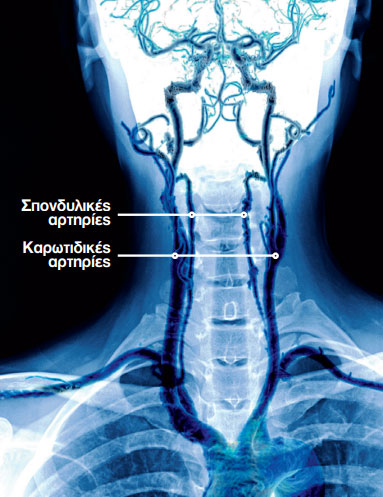

Οι δύο αρτηρίες στην πρόσθια πλευρά του αυχένα (καρωτιδικές αρτηρίες) και δύο ακόμη αρτηρίες στην οπίσθια πλευρά του (σπονδυλικές αρτηρίες) είναι γνωστές ως αυχενικές αρτηρίες.

Η ρήξη (σχίσιμο) στον εσωτερικό χιτώνα του τοιχώματος μιας από αυτές τις αρτηρίες, η οποία ονομάζεται διαχωρισμός αυχενικής αρτηρίας, έχει ως αποτέλεσμα τη διαρροή αίματος μεταξύ των τριών χιτώνων του τοιχώματος της αρτηρίας (και τον διαχωρισμό τους).

Ο σχηματισμός θρόμβου, ως φυσική απόκριση του οργανισμού για να σταματήσει την αιμορραγία, μπορεί να έχει αντίθετα αποτελέσματα, επειδή ένας

ευμεγέθης θρόμβος είναι πιθανό να εμποδίσει τη ροή του αίματος μέσω της αρτηρίας ή να αποσπαστεί και να σφηνώσει σε μια εγκεφαλική αρτηρία.

Και τα δύο αυτά ενδεχόμενα μπορούν να αποτελέσουν αιτία εγκεφαλικού.